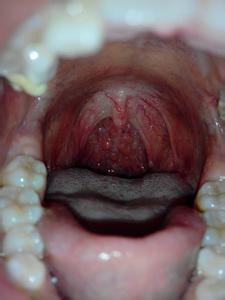

阅读配图

每天早上刷牙时,很多人会感到恶心,有的还会呕吐。这是为什么呢?其原因如下: